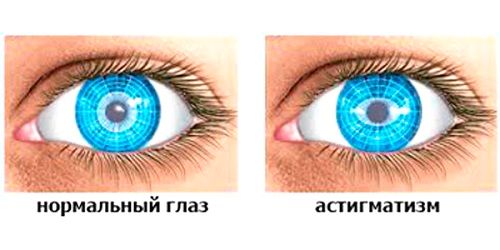

У нормі промені, які проходять через рогівку, фіксуються в одній точці. При астигматизмі вони утворюють лінію. Промені, які повинні сходиться на сітківці, можуть сходитися за або перед нею. Я не буду вдаватися в подробиці і пояснювати вам закони фізики. Головне - це те, що ми змогли вловити суть процесу.

Які існують види астигматизму? Насправді це захворювання має безліч класифікацій і багато поділів. Почнемо з самого простого, він може бути вродженим або набутим. Природжений також прийнято називати функціональним, якщо він не впливає на гостроту зору, тоді це вважається нормою.